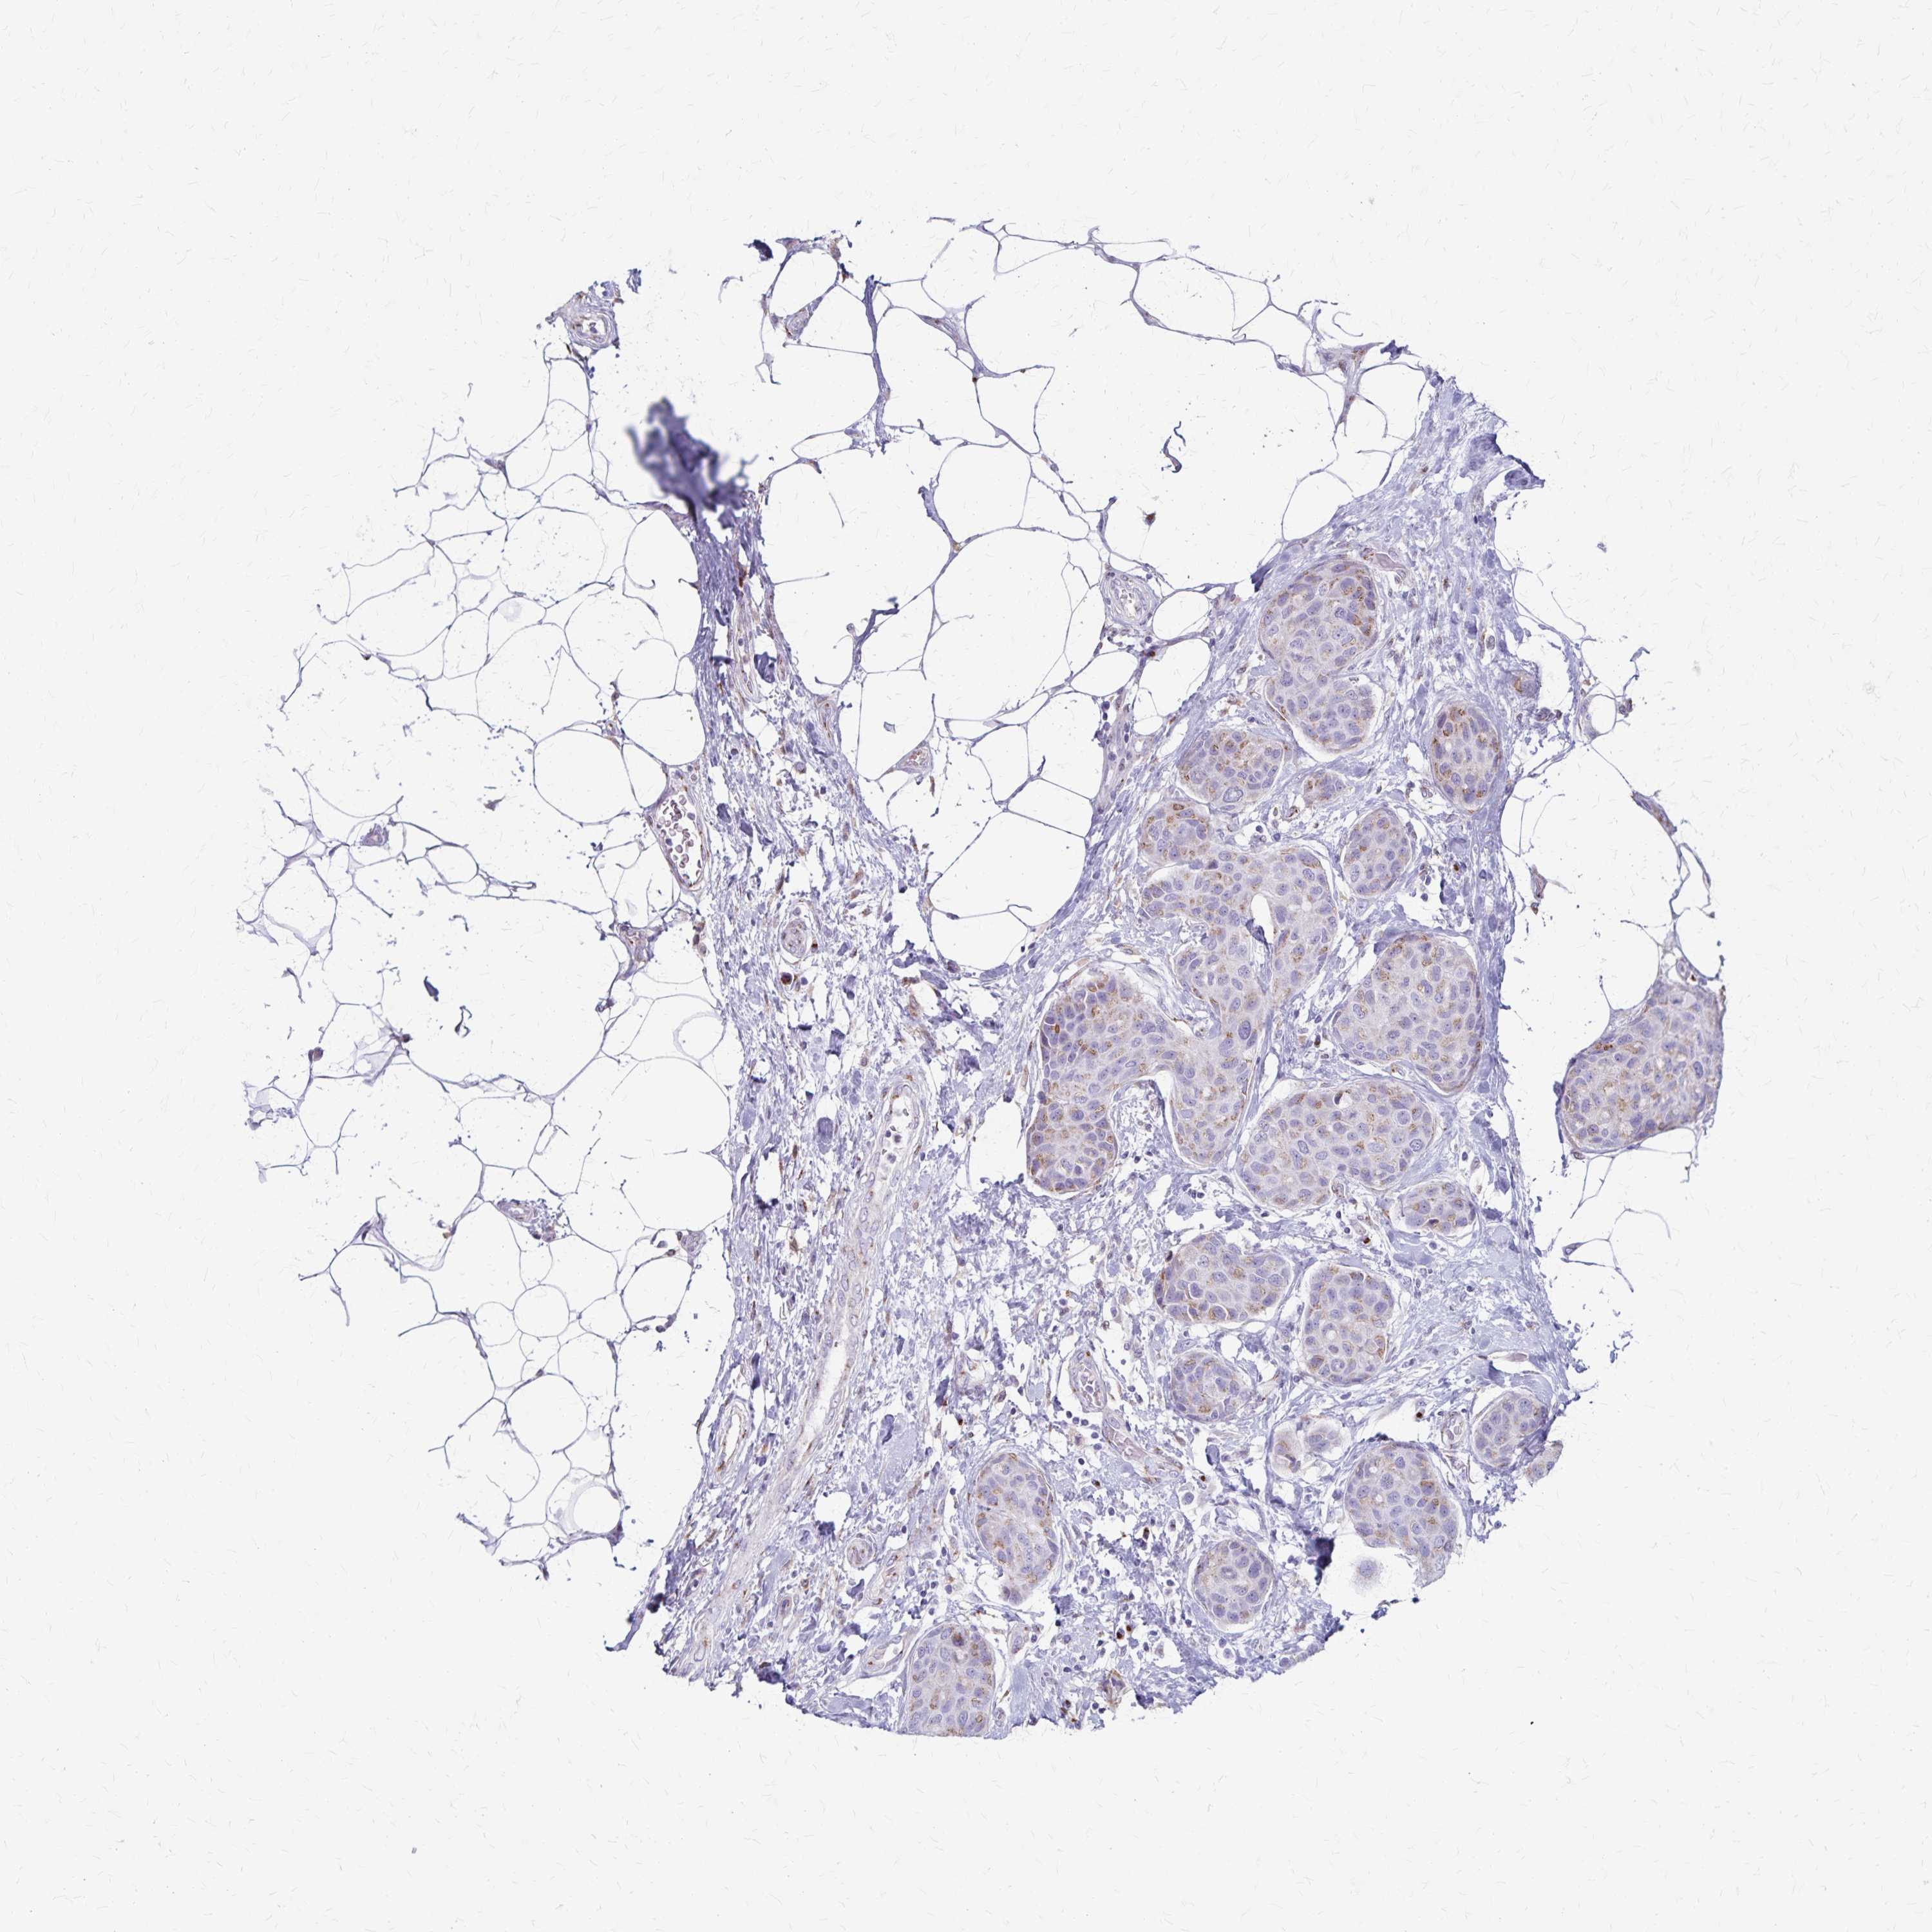

CANCER BREAST CANCER Show tissue menu

Breast cancer

Human cancer